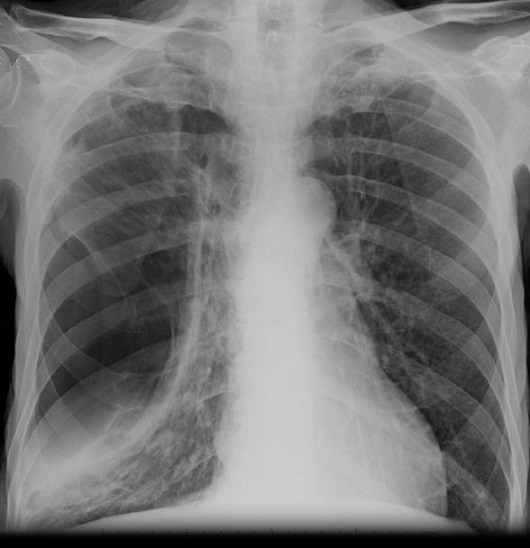

Aspect

radiologique d'un tension pneumothorax

du poumon droit avec image de collabe en

moignon du poumon droit , deviation du

mediastin à gauche , ecrtation de espace

intercostale et depress de la coupole

diapragmatique droit . |

Image radiologique d'un

pneumothorax traumatique par fracture

des côtes du poumon droit . Image

radiologique peut eliminer facile la

degree de trauma et de la lesion sur la

TDM fenetre parenchymateuse . |